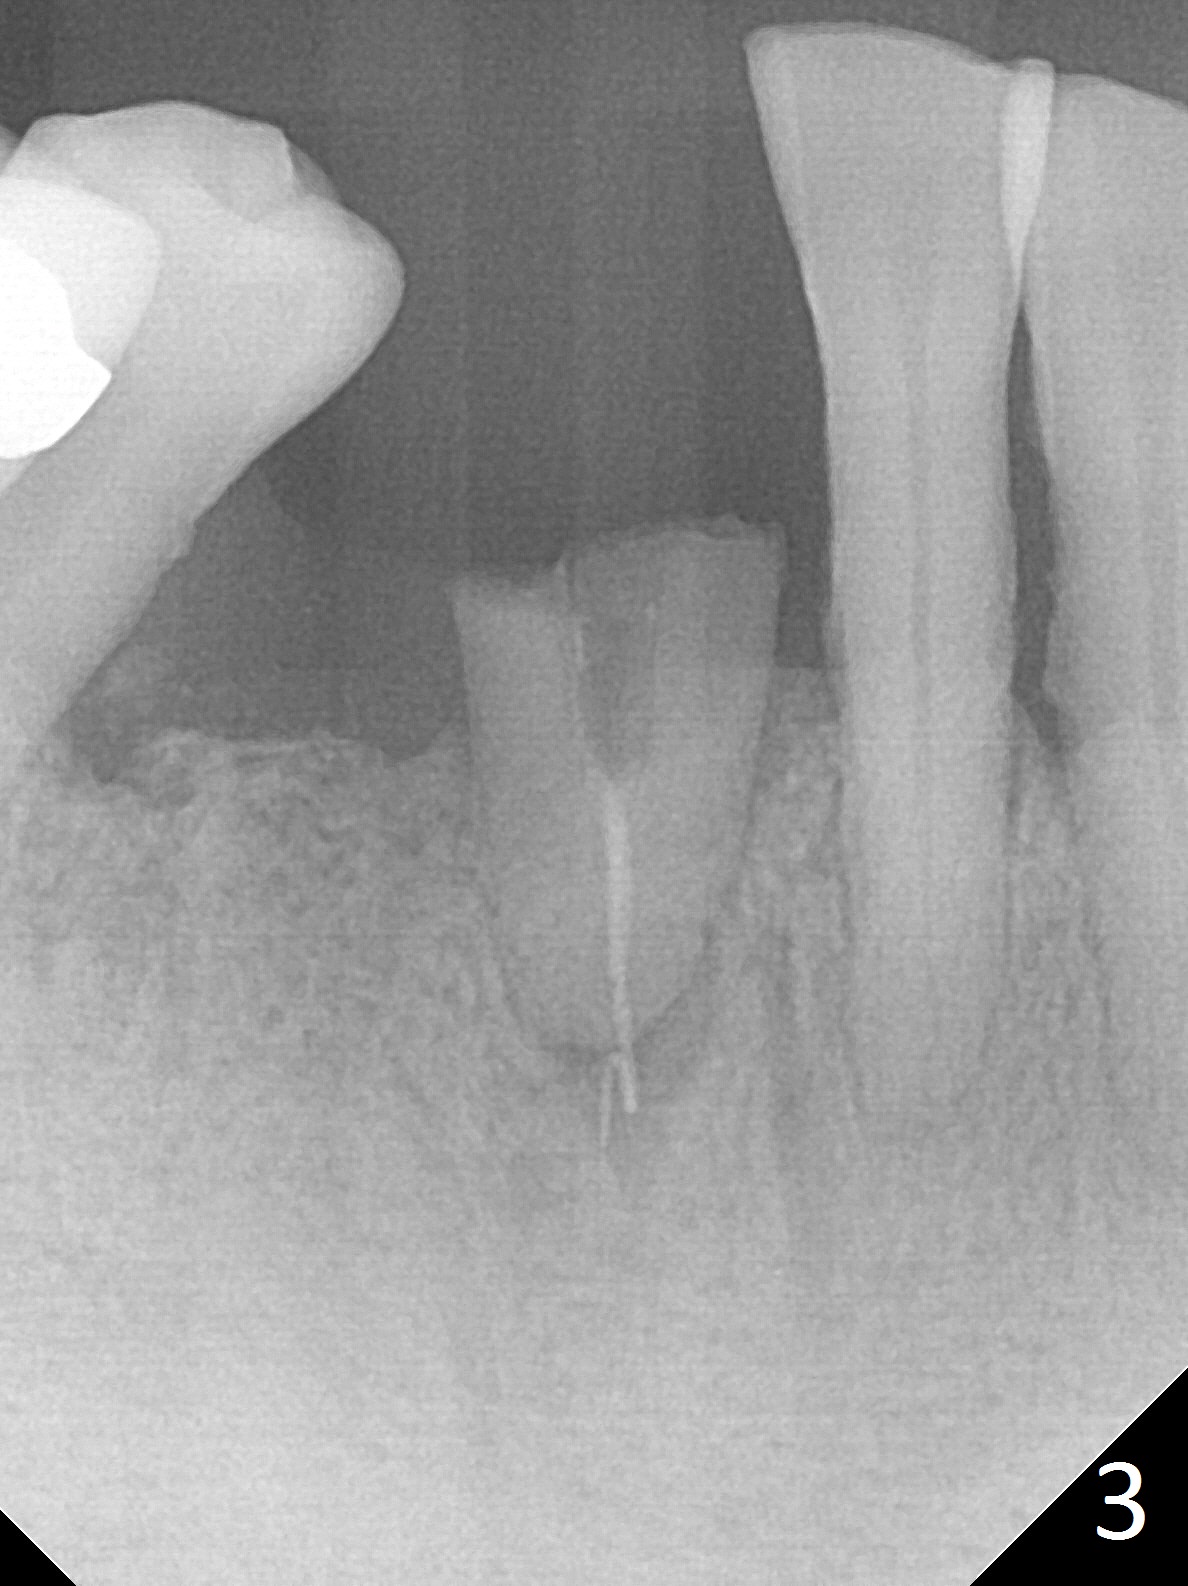

The lower dentition is special, consisting of a residual root (Fig.1 ^), 2 incisor (I), 1 canine (C), 1 premolar (P) and 1 molar (M). The residual root looks like an incisor with rotation of 90º (Fig.2,3). Osteotomy is initiated (Fig.4) for a 3x16(2) mm 1-piece implant (Fig.5 with 45 Ncm). The implant is being placed as distal as possible (Fig.4 arrow) so that a large canine-like provisional is to be fabricated in the large edentulous space (Fig.8,9) after bone graft (Fig.6,7 *). The gingiva around the provisional (Fig.10 P) remains healthy 11 days postop with occlusal clearance against the opposing dentition (Fig.11). The implant threads are not exposed with the help of bone graft 3 months 1 week postop (Fig.12). The gingiva around the implant is healthy (Fig.13). Soft tissue socket is formed by the provisional (Fig.14 *).